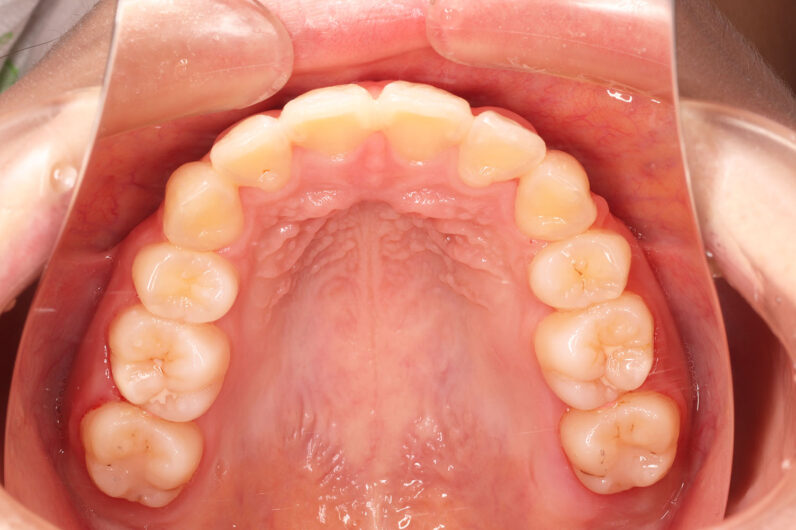

他院から紹介の患者さんです。 前歯、下の歯のガタツキをきれいにしたいということで治療を決断されました。

上顎前歯6mm、下顎前歯2.5mmの前突の状態で、口唇も前突しています。 小臼歯抜歯したスペースを使い、叢生(がたつき)と前突した前歯の後退を目標にしました。 この方も希望により、アンカースクリューは使用せず、通常の顎間ゴムで対処してもらいました。

マルチブラケット 動的治療期間 3年5か月 調整回数29回

治療後は前歯は後退し、前歯の傾斜度も良くなっています。 口唇の緊張感も改善し、エステティックラインも綺麗になりました。